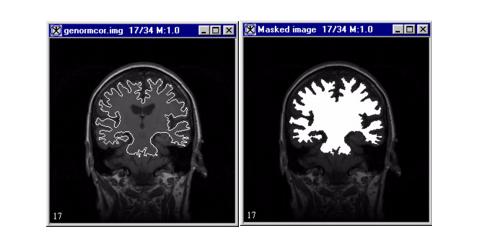

When you apply this algorithm, enter the intensity value that fills the mask (contour). Then, indicate whether you want the algorithm to fill the area inside or outside of the contoured areas. When this algorithm runs, it determines which areas are contoured and fills the areas inside or outside of the contour with the specified intensity value (refer to Figure 1).

Figure 1. Mask algorithm processing